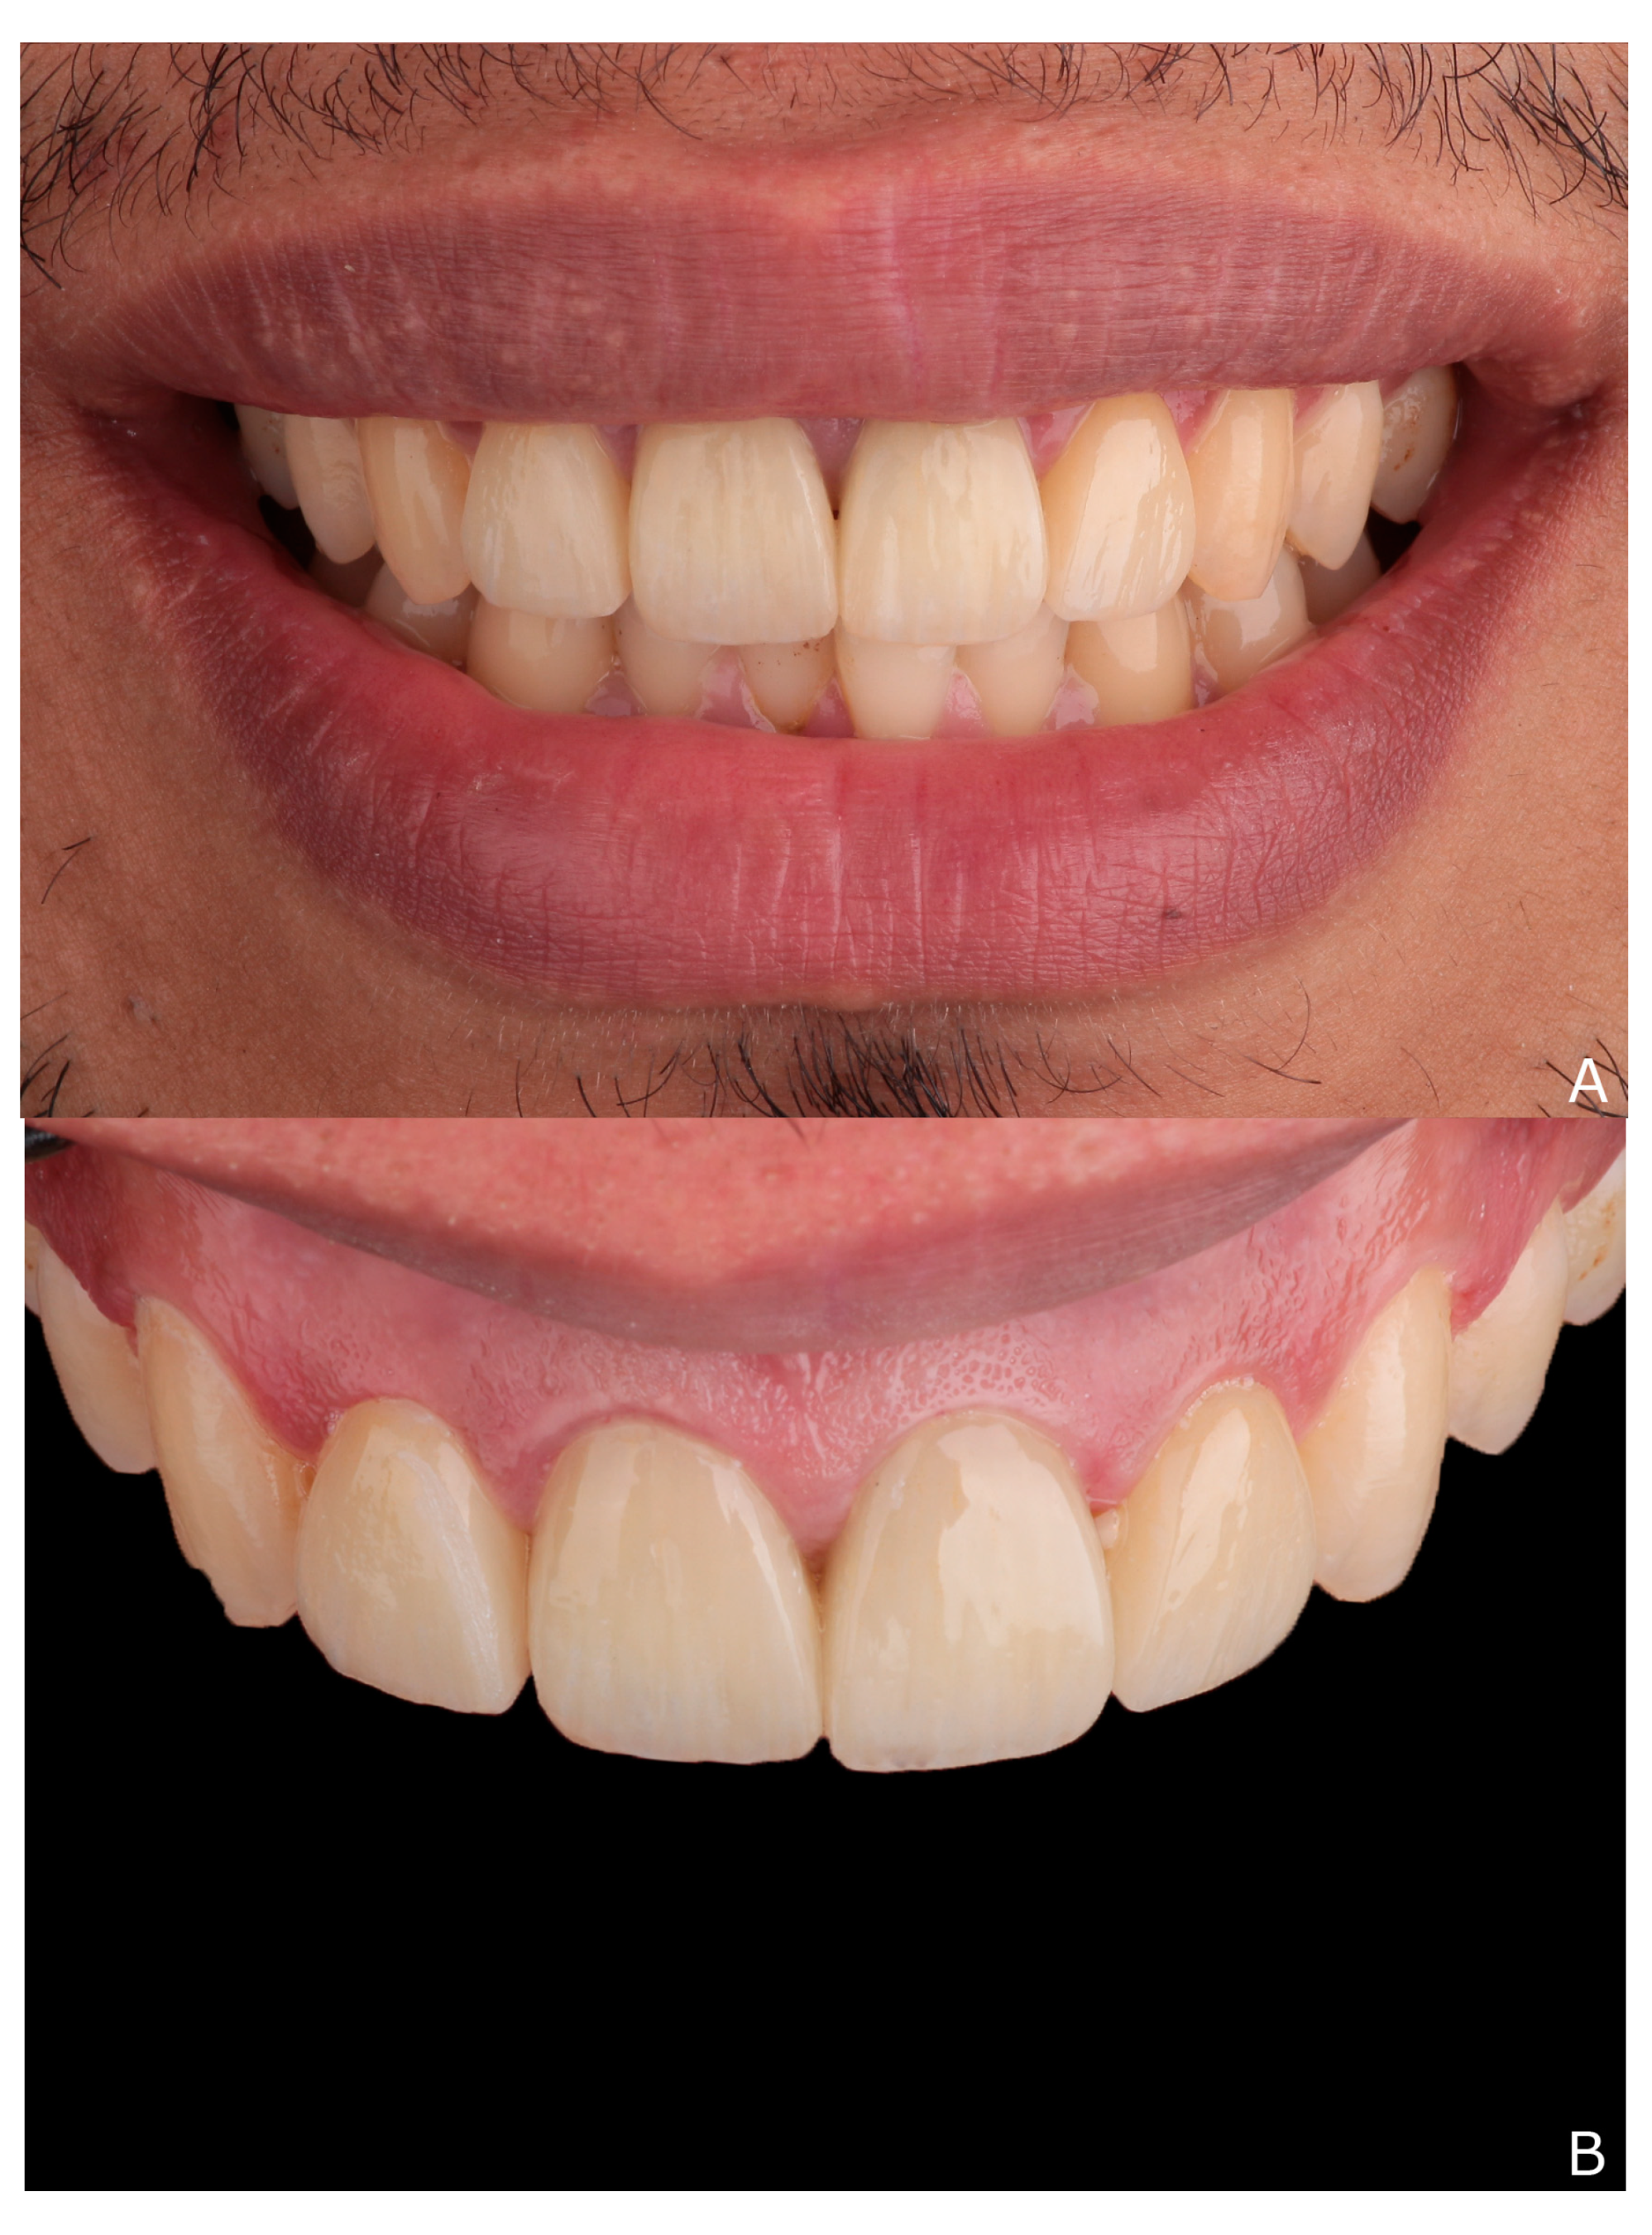

2. Clinical Report